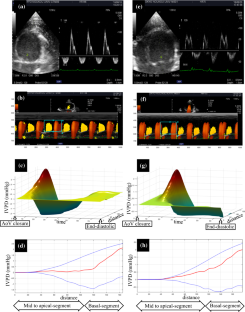

To study the diastolic functions using color Doppler M-mode (CDMM) for noninvasive analysis of the intraventricular pressure difference (IVPD) in diabetic rats.

DM rats showed higher systolic blood pressure and diastolic dysfunction, i.e., decreases in several parameters such as E, E/A, TDIs, and IVPDs, compared to the controls. Moreover, obvious cardiac fibrosis was seen in perivascular and interstitial tissues, but there were no notable differences in terms of gross lesions.

Because of the noninvasive nature of CDMM, IVPD and other conventional echocardiographic parameters can be used as reliable indicators generally for evaluating cardiac function and particularly the change in intraventricular pressure.